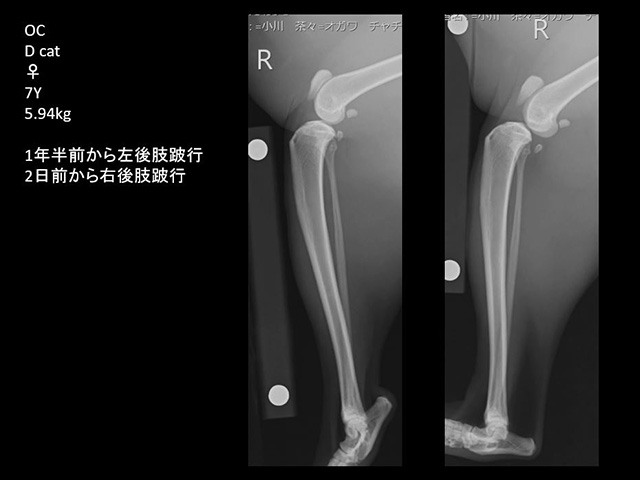

膝関節の前十字靭帯断裂は、外傷や靭帯変性などに起因して生じます。

これまで、主に体重が重く、活動性の高い中・大型犬が外科治療の対象でした。

最近では小型犬にも多く見られ、前述の膝蓋骨内法脱臼が長い間放置されていることに起因して発症しているようです。